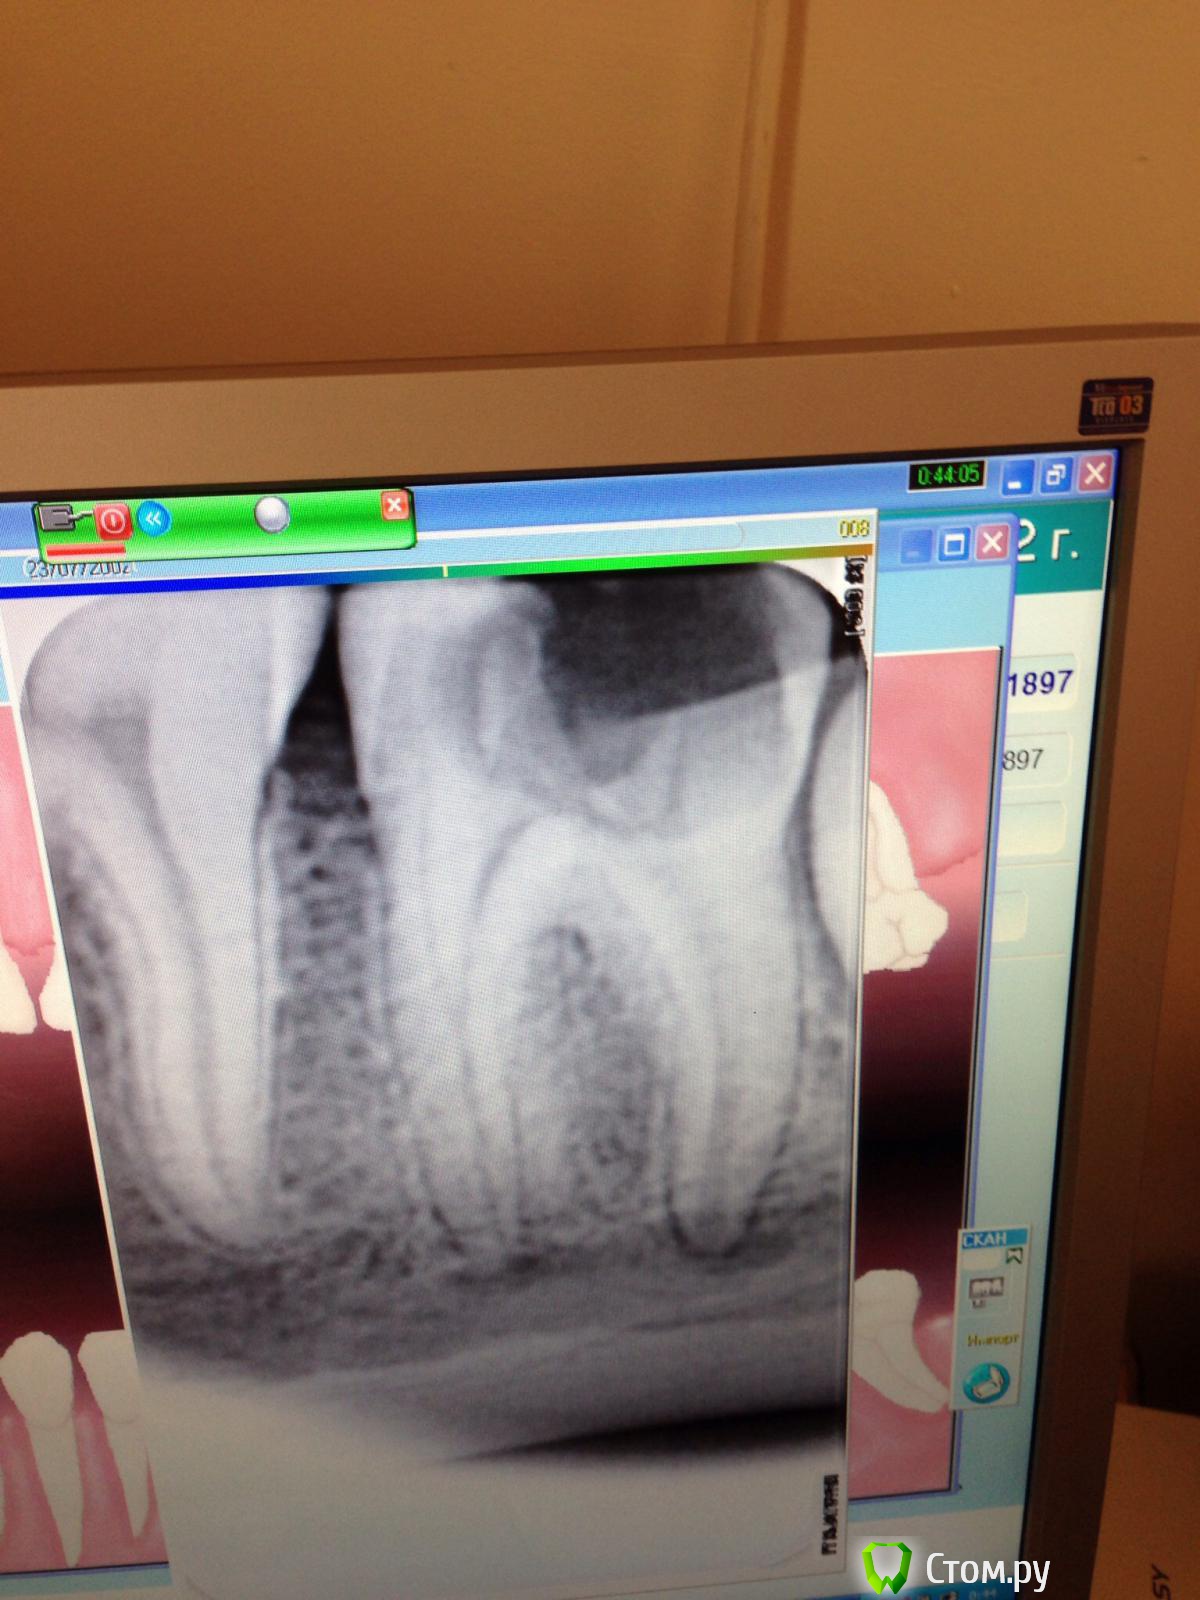

Zuri Опубликовано 19 июля, 2014 Автор Поделиться Опубликовано 19 июля, 2014 Рентген бы посмотреть....Вот снимок Ссылка на комментарий

Чертков Александр Опубликовано 19 июля, 2014 Поделиться Опубликовано 19 июля, 2014 Вот снимок А панорама есть? Ссылка на комментарий

Чертков Александр Опубликовано 21 июля, 2014 Поделиться Опубликовано 21 июля, 2014 К сожалению, нет. (На мой взгляд - лучше убрать. Расположение зуба таково, что при его постепенном прорезывании возникнет скученность во фронте (если её уже нет) и гигиеническая проблема по дистальной поверхности седьмого зуба. Да, он пока ещё покрыт костью, но эта тоненькая кортикальная пластинка скоро исчезнет и будет систематический перикоронарит. Ссылка на комментарий

Zuri Опубликовано 21 июля, 2014 Автор Поделиться Опубликовано 21 июля, 2014 На мой взгляд - лучше убрать. Расположение зуба таково, что при его постепенном прорезывании возникнет скученность во фронте (если её уже нет) и гигиеническая проблема по дистальной поверхности седьмого зуба. Да, он пока ещё покрыт костью, но эта тоненькая кортикальная пластинка скоро исчезнет и будет систематический перикоронарит. Спасибо большое. ) Скученность, действительно, есть. Надо было своевременно убрать восьмерку и с другой стороны. (( значит, буду удалять. Ссылка на комментарий